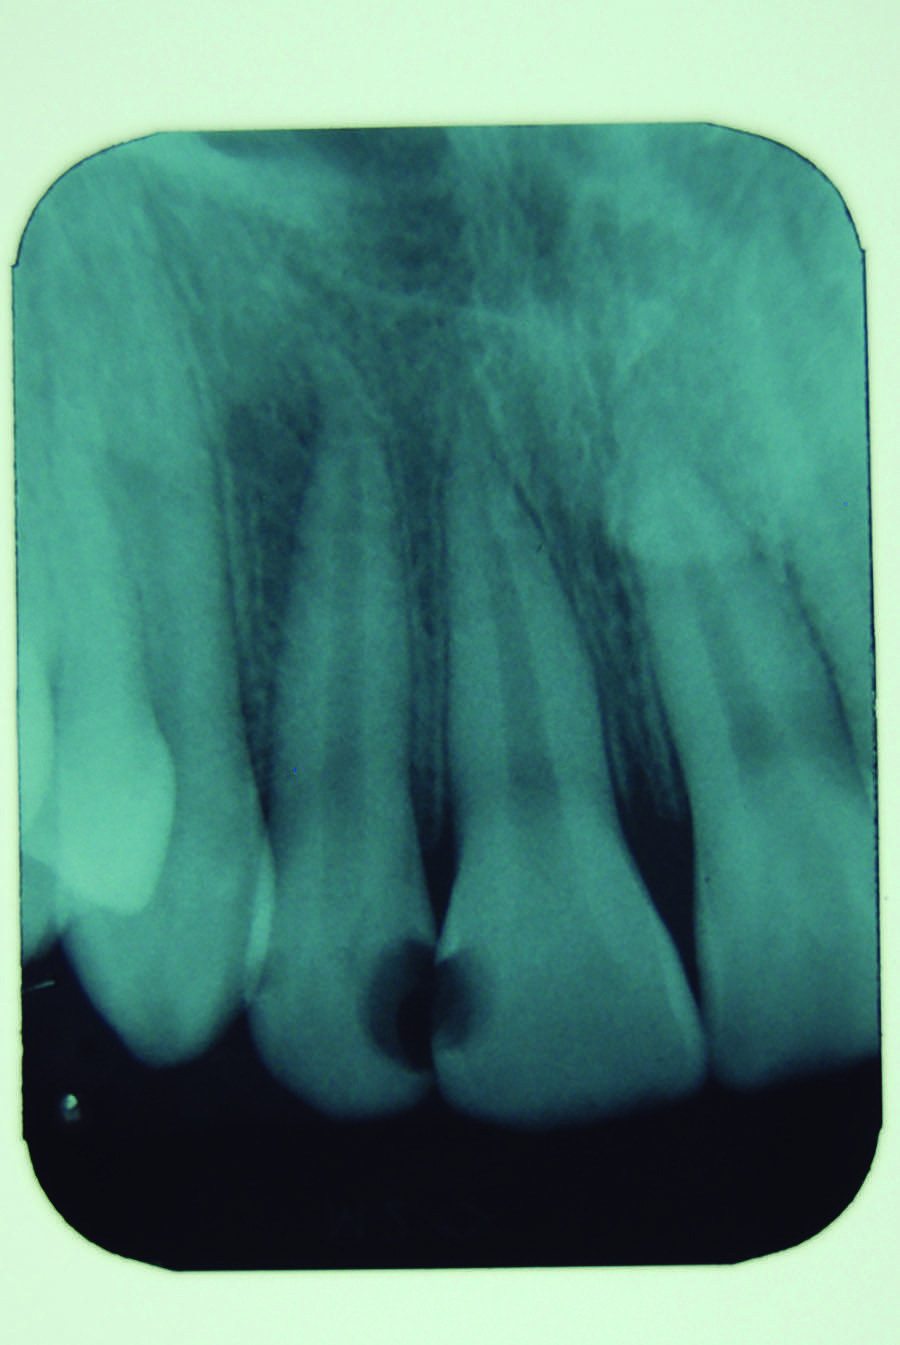

A 12-year-old male presented with extensive carious lesions observed on teeth Nos. 7 through 10, which were accompanied with gingivitis (Figure 1). The pulpal condition was verified through thermal sensitivity tests and vertical percussion, both being satisfactory (Figure 2). The proximity of the lesions with the pulp chamber and the absence of periapical lesions, especially in the right lateral incisor, were observed by the radiographic examination (Figure 3).

Fig 3. Radiographic findings showing the proximity between carious lesions and the pulp chamber.

Figure 3